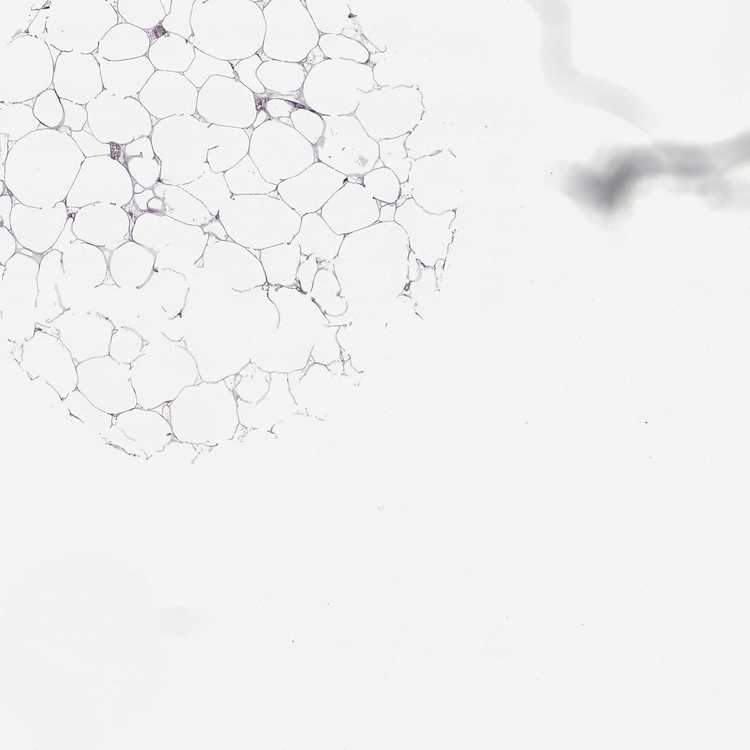

BREAST - Antibody stainingi

Antibody staining in the annotated cell types in the current human tissue is reported as not detected, low, medium, or high, based on conventional immunohistochemistry profiling in selected tissues. This score is based on the combination of the staining intensity and fraction of stained cells.

Each image is clickable and will lead to virtual microscopy that enables deeper exploration of all samples and also displays staining intensity scores, fraction scores and subcellular localization as well as patient and tissue information for each sample.

Antibody HPA073724

Adipocytes Not detected

Glandular cells Not detected

Myoepithelial cells Not detected